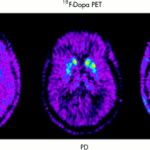

Utilizzando il profilo di espressione genica, un metodo per misurare l’attività di migliaia di geni, i ricercatori hanno studiato i neuroni dopaminergici del mesencefalo, che sono le cellule nervose che utilizzano la dopamina per inviare segnali ad altre cellule nervose. Questi neuroni sono noti per degenerare nel morbo di Parkinson.

Secondo Parkinson Society Canada, quasi 100.000 canadesi sono affetti dal morbo di Parkinson. Questa malattia neurodegenerativa progressiva colpisce prevalentemente il movimento controllato a causa della perdita di cellule responsabili della produzione di dopamina, che funge da messaggero tra le cellule cerebrali che controllano i movimenti del corpo.